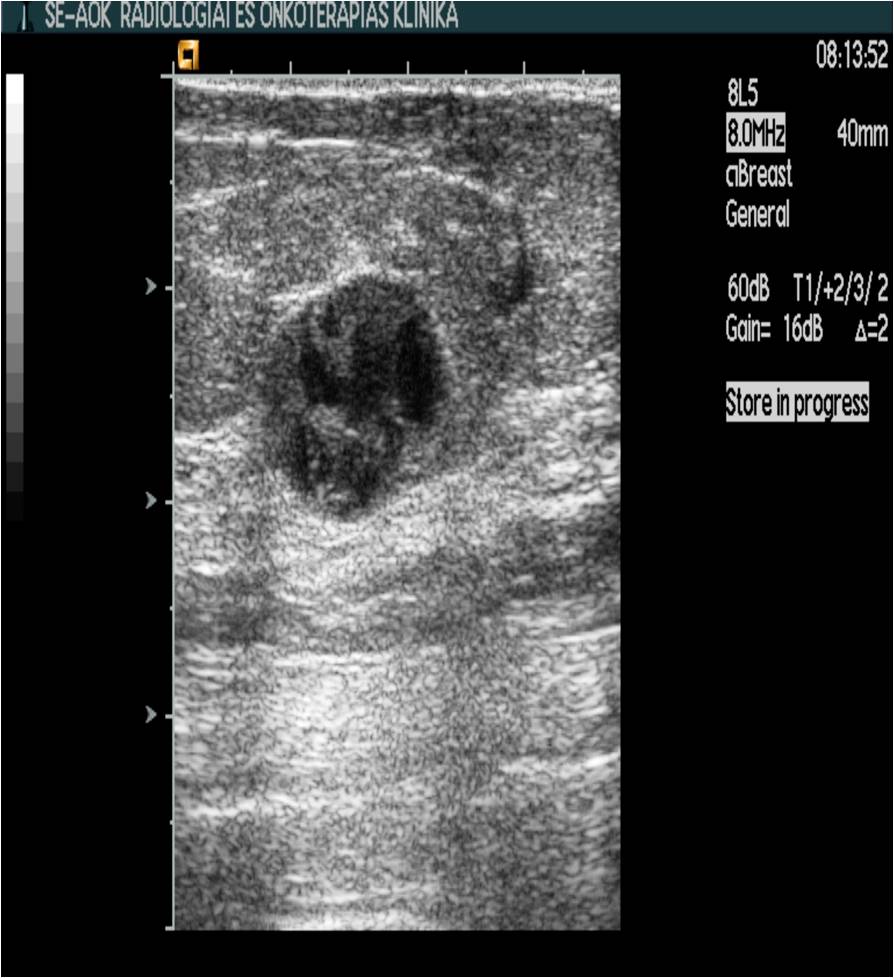

Ultrasonography can help in their differentiation; can depict anechoic cystic lesions (Picture17.) or solid masses (Picture 18.). These lesions usually each have a smooth, sharp edge and echo-enhancement can appear behind them. Rarely, cysts contain tumors. (Picture19.).

Ill-defined margins, with uneven contours and blurred edges are usually characteristic of malignant lesions. During ultrasound examination echo-attenuation occurs frequently behind these inhomogeneous hypo-echogenic masses (Picture 20).